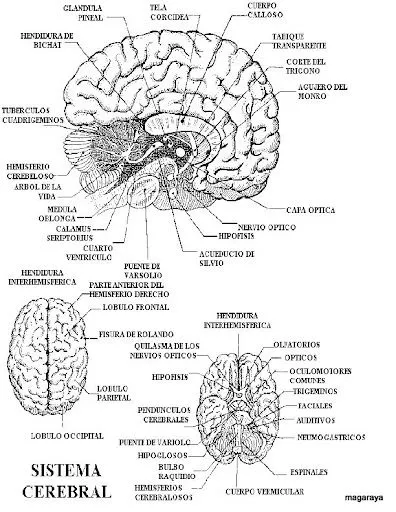

Encéfalo y sus partes para colorear

Descubre dibujos del encéfalo y sus partes para colorear, ideales para aprender anatomía de forma divertida y educativa.

Dibujo del encefalo y sus partes para colorear - Imagui

LAMINAS DEL CUERPO HUMANO PARA COLOREAR Y APRENDER | Dibujos para ...